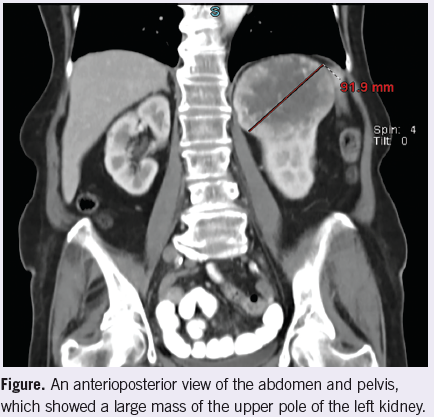

Radiology. A CT scan of the abdomen and pelvis showed a mass in the upper pole of the left kidney (Figure).

The clinician’s knowledge of the patient and family is also useful in determining whether or not further studies are appropriate. In the above patient, her physician did not suspect depression or cognitive impairment. Her chronic medical problems were well-controlled. The patient had 2 daughters—both nurses—who provided close observation and care to the patient. In light of the patient’s history of adenomatous polyps, anemia, and microscopic hematuria, colonic or genitourinary malignancy were high in the differential. Therefore, a CT scan of the abdomen and pelvis seemed to be the best, first imaging test to pursue.